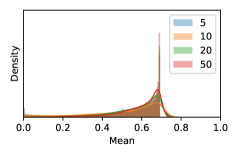

To model how different classifiers will respond to a given input , we assume that the prediction from classifier is sampled from a beta distribution that is characterized by two parameters by and . We further assume that is fixed to the same constant value for all ’s. Under this assumption, each input can be described by ( can be calculated since is fixed), easing further analysis. The Severity Level (SL) of the case represented by image can be characterized by the parameter . The larger the value of , the more severe the case of is. When and are close, the case is ambiguous as the distribution shifts towards being symmetric (i.e. signifying much disagreement among classifiers) rather than being one-sided (i.e. consensus among classifiers that is negative or positive). We provide a set of examples in Figure 2 and also Figure S.8 in the supplementary materials showing how the beta distribution can be used to capture diverse predictions given by an ensemble learner.

We conducted a case study on diagnosing diabetic retinopathy with ensembles of DL models. For benchmarking the performance of our ensemble-based solutions under the scheme described in Sec.3.3, we used two popular collections of diabetic retinopathy image data, the Kaggle Diabetic Retinopathy dataset [22] (hereafter referred to as “Kaggle-DR”) and the Messidor-2 dataset [23], each respectively consisting of and high resolution images. Diabetic retinopathy is graded into five SLs, as displayed in Figure 2. Following the problem setup used in previous papers [24], we trained models to distinguish the referable (SL2-4) cases from the non-referable ones (SL0 & SL1) (see Section B.1 for more detailed descriptions). We also tested our trained ensemble models on two o.o.d. image datasets (ImageNet [25] and CIFAR-10 [26]) to examine their capabilities of identifying o.o.d. inputs (see Section B in the supplementary materials).

In contrast, the MC-dropout method showed the worst overall performance among the three, as it can be seen from the high ratios of SL0 examples among the uncertain negatives in Figure 4. The histograms in Figure 2 provides another perspective to look into the phenomenon, where a decent proportion of MC-dropout model’s predictions on SL0 inputs entailed low confidence (far from 0 or 1), which from another angle explained why MC-dropout was less specific in terms of lower FNP; many no-DR inputs (i.e. SL0) were erroneously assigned high uncertainty by MC-dropout models.

As discussed in Section 5.1 and Section 5.3 in the main paper, the mean metric and the stacking ensemble will have better performance in the precision (specificity) on the ambiguous data. Here, more detailed results are shown in Figures S.3 & S.6 and Table S.1. Figures S.3 & S.4 show the histograms of the uncertainty score for Kaggle-DR and Messidor-2 datasets that are the in-distribution (i.d.) dataset in our experiment and FigureS.5 & S.6 show the histograms for ImageNet and CIFAR-10 datasets, which is the o.o.d. datasets in our experiment. Each group of histograms contains results from the three evaluated ensemble methods (stacking ensemble, MC-dropout and TTA) and the three uncertainty metrics (mean, var and kl). Additional detailed results not displayed in Figure 4 can be found in Table S.1, which shows the proportion of the data of different SLs varies across different . For comparison, we also included in Table S.1 the results from single learners, and the proportions of data of different SLs (before any selection was made).